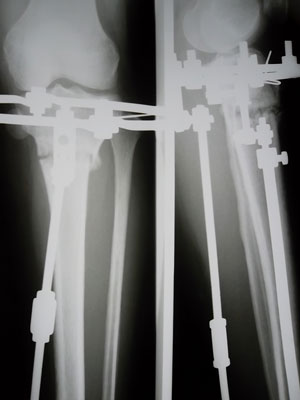

Костная мозоль зреет хорошо, к концу месяца можно приезжать на снятие аппаратов.

У Вас по 2 спицы в каждом кольце осталось???

Да, у меня на каждой ноге по две спицы, я хорошо себя чувствую, легче двигаюсь и намного легче поднимаюсь по лестнице))))

Чувствую себя хорошо, в общем у меня ломались спицы 6 раз, шестой раз было на 79 день со дня операций...осталось так же по 2 спице на верхней части аппарата)))) Скоро наступит день снятия УРРА!!!